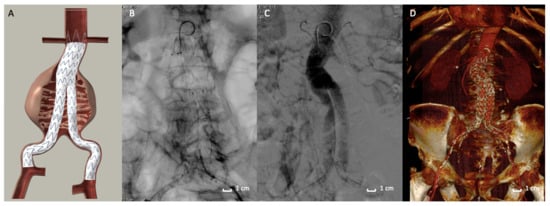

The Nellix System (Endologix Inc., Irvine, CA, USA) for endovascular aneurysm sealing (EVAS) was introduced as a novel approach to the treatment of AAA [58] in 2013. The EVAS procedure is conceptually distinct from EVAR: the Nellix device is designed to seal and obliterate the aneurysm lumen and not to exclude it (Figure 2B,C).

The device consists of two balloon-expandable stents supporting the aorta flow channel. The system is inserted into the aorta in a similar way to EVAR. By using guidewires, the system is advanced into the aorta through the femoral arteries. The catheter sheaths are then pulled back, deploying the device, which expands from the non-aneurysmal aorta proximally to the iliac arteries distally. The non-porous PTFE-based endobags are then filled with the biocompatible polyethylene glycol polymer (Figure 2B,C), which adjusts the endobag to fit the aneurysm sac lumen. The bio-stable cross-linked polymer inflating the endograft envelope in opposition to the aortic wall mimics the process of injection molding. Thus, high conformability is achieved, as the device is molded in-situ to the specific patient anatomy to accomplish a customized seal. Once this configuration is completed, the polymer cross-links to form a ‘personalized’ prosthesis [59].

Figure 2. Nellix stent graft. (A,B) Picture of Nellix endograft during the endobags’ polymer filling maneuvers. The asterisk (*) indicates the endobags that adapt to the morphology of the entire aneurysm sac. (C) Axial Computed Tomography Angiography detail of a Nellix endograft implanted. The stent grafts (arrows) are located in the middle of endobags, which are filled with polymer (*). (D) Intraoperative image of the Nellix stent graft deployed with angiographic contrast medium that highlights the good patency of the endograft and the exclusion of AAA. (E) 3D volume rendering of Computed Tomography Angiography at 3-months follow-up post-implantation that reveals a good aneurysm exclusion. The asterisk (*) indicate the polymer-filled endobags.